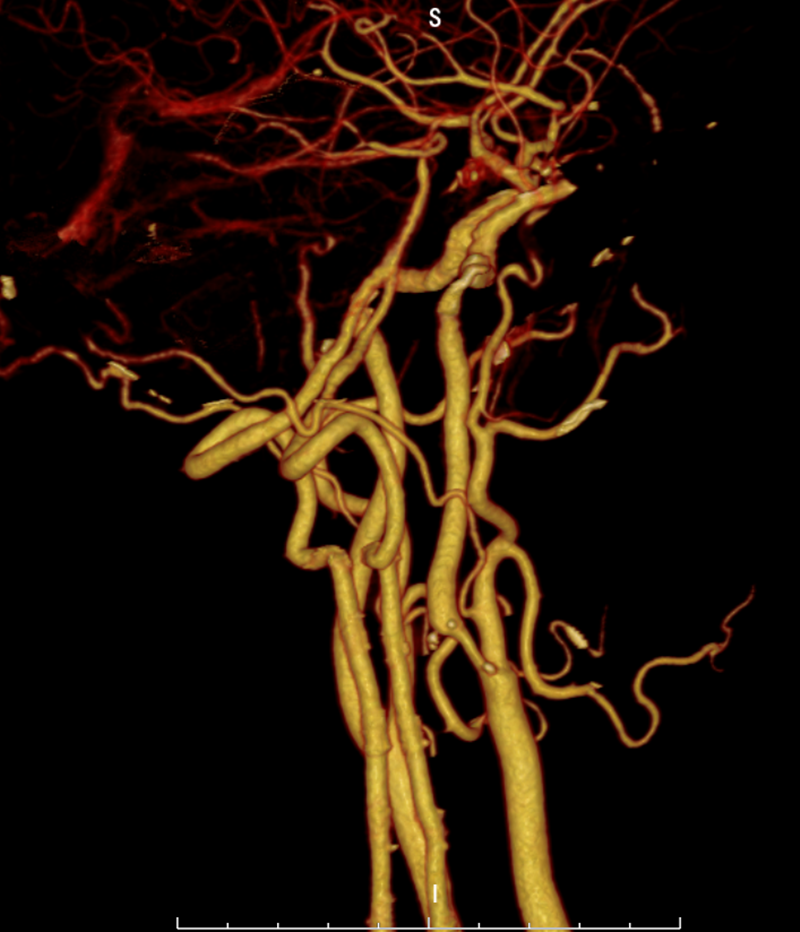

患者,男性,70岁,因“反复头晕2年”来县二院就诊,门诊行头颈部CTA检查:右侧颈内动脉C1段起始部中-重度狭窄。(如下图)

该患者CTA检查结果显示为右颈内动脉起始部局限性重度狭窄,且狭窄程度约为80%。由于患者病情十分严重,如不及时进行治疗可能导致急性血管栓塞闭塞、偏瘫、昏迷,甚至危及生命。